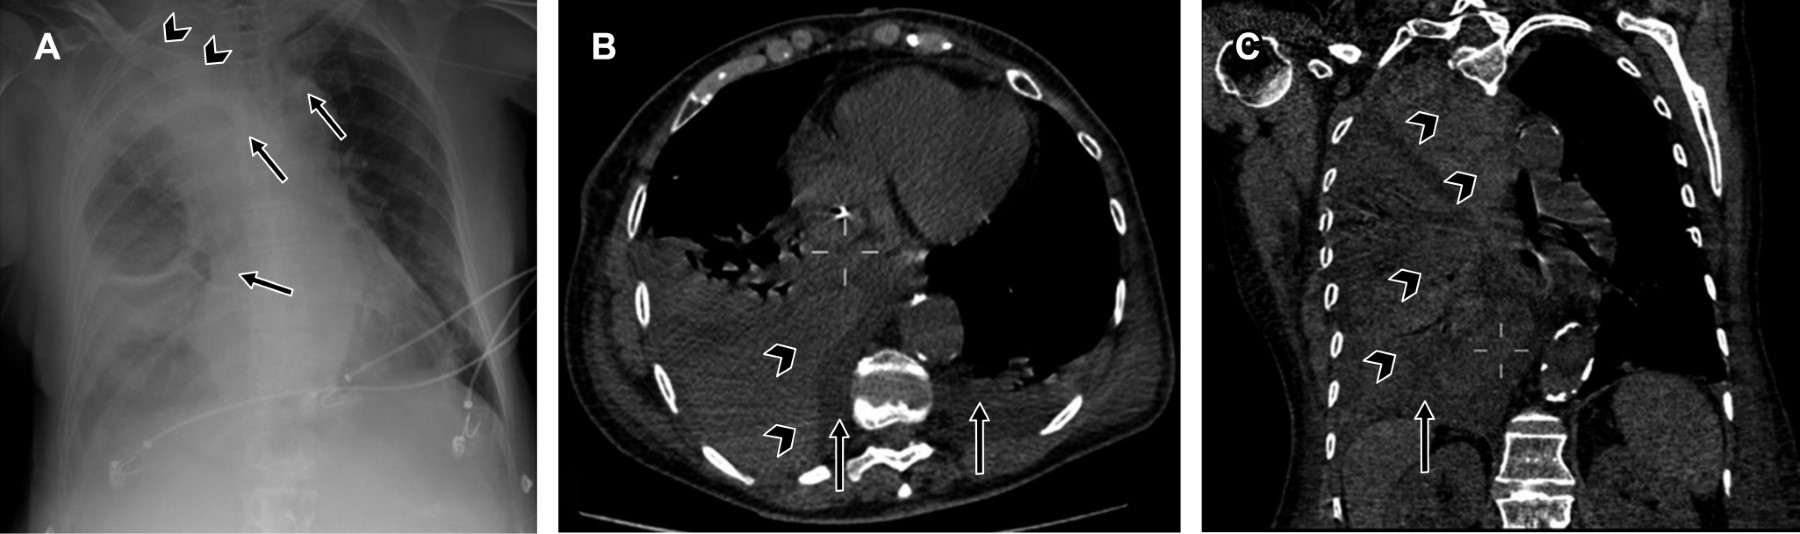

El neumotórax es la segunda complicación inmediata más frecuente y ocurre en 5% de los procedimientos de colocación de catéter venoso central. Se asocia con mayor frecuencia al acceso subclavio, por lo que se recomienda verificar su localización mediante una radiografía de tórax posterior a cualquier intento, sea éste exitoso o no.3 El neumotórax ocurre cuando se produce la pérdida de la presión negativa del espacio pleural, que condiciona colapso del parénquima pulmonar.27 En la radiografía de tórax, el neumotórax usualmente se detecta por la presencia del signo de la "línea blanca pleural visceral", condicionada por la separación de las capas (visceral y parietal) debido a la interposición de aire libre en el espacio pleural,28 lo que hace visible una línea opaca delgada, bien definida, delineada por el pulmón lúcido que presenta componente intersticial y por aire más oscuro del neumotórax adyacente a la pared torácica (Figura 8).27

Otros hallazgos incluyen el aumento de la radiolucidez extrapulmonar y el desplazamiento mediastínico hacia el lado contralateral cuando el neumotórax es prominente o se encuentra en tensión.27

Las radiografías de control en este tipo de pacientes por lo regular son anteroposteriores y en decúbito supino, por lo que los datos radiológicos de neumotórax son más difíciles de detectar. Un signo indirecto útil para inferir o sospechar la presencia de un neumotórax en una radiografía tomada con el paciente en decúbito supino es el signo del surco profundo (Figura 8B), donde el ángulo costofrénico lateral se vuelve más profundo y lúcido en comparación con el contralateral.27 Este signo se produce por el aire que se acumula en las partes no dependientes de la pleura (anterior y basal), en contraste con la posición vertical donde el aire se acumula en el ápice.28

También se observará la línea pleural visceral en la región apicolateral, especialmente al aumentar el tamaño del neumotórax.27